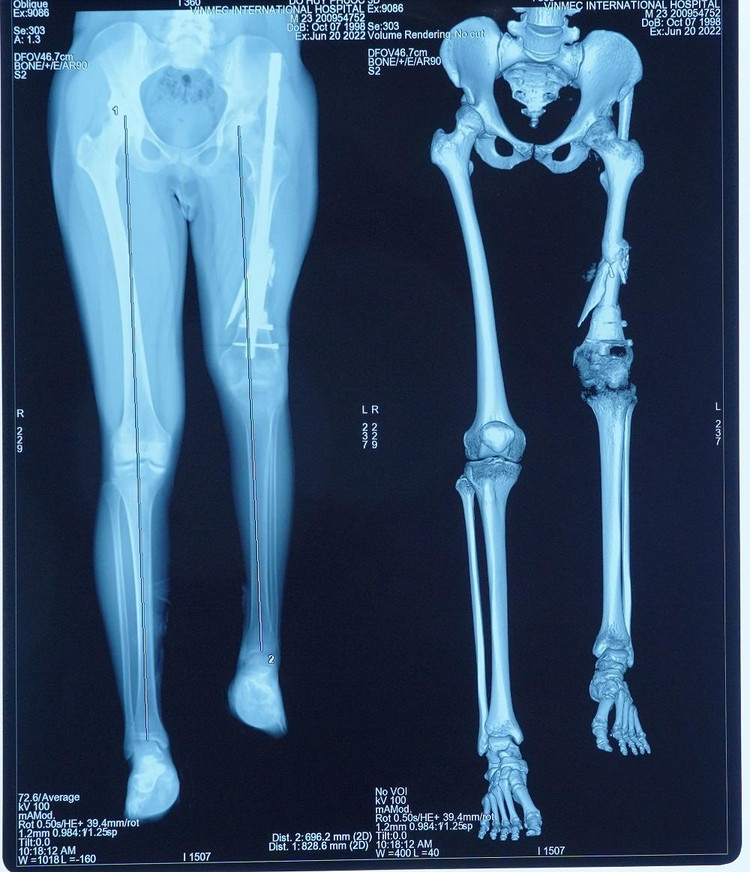

Sau khi chân trái được kéo dài tới 13cm, anh Đỗ Huy P. (24 tuổi, Đắk Lắk) đã có chiều dài 2 bên chân tương đương nhau. Về quê sau gần 3 tháng nằm điều trị ở Hà Nội, anh P. bỏ được một bên nạng, chỉ cần dùng nạng cho bên chân đã kéo, đồng thời rất tích cực tập phục hồi chức năng để cơ chân khỏe và nâng đỡ tốt. Theo tiên lượng của các bác sĩ, trong vòng 6 tháng anh có thể đi lại hoàn toàn bình thường.

Sau nhiều lần thăm khám, hội chẩn, GS. Dũng và ekip đã đi đến phác đồ điều trị 2 giai đoạn: Gỡ dính và kéo phần cơ đang co rút ra tối đa có thể, sau đó thực hiện phẫu thuật ghép xương đùi và đầu gối nhân tạo bằng vật liệu y sinh. Toàn bộ kích thước, trọng lượng xương nhân tạo sẽ được tính toán bằng công nghệ 3D để đảm bảo gần với chân lành nhất. Bệnh nhân đã 24 tuổi và ổn định chiều cao nên không lo bị chênh lệch chi và tránh nguy cơ gãy xương lần nữa, như vậy sẽ đi lại được bình thường.

| Phương pháp này đã thực sự mang lại cuộc sống mới cho bệnh nhân sau khi khắc phục được độ chênh lệch giữa 2 chân lên tới 13cm |